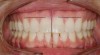

Figure 6  Facial esthetics starts with the maxillary incisal edges following the lower lip in the smile, but involves much more.

Figure 6